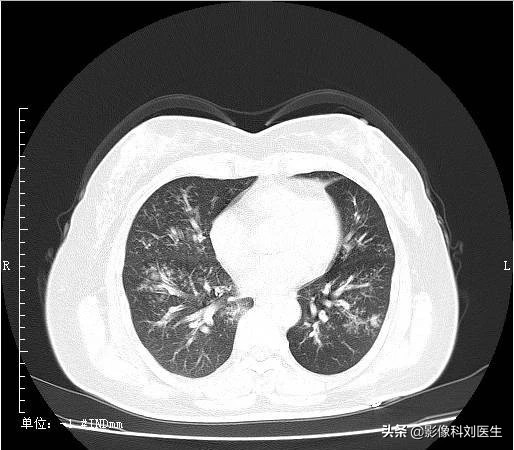

支气管肺炎累及多肺叶、多肺段,沿支气管血管束分布,下叶多见,常表现为多发、边界不清的结节样阴影,为腺泡结节,多位于小叶中央;部分呈磨玻璃密度影,部分病灶可融合;由于炎症导致终末细支气管阻塞,可引起局限性肺气肿,当化脓感染时,可出现大小不等的空洞。

CT 表现:表现为两肺中下野内中带云絮状、斑片状、结节状高密度影,沿支气管走行分布,边缘模糊,散在的小片状影,可以融合成大片状,可并发小叶性肺气肿及肺不张。